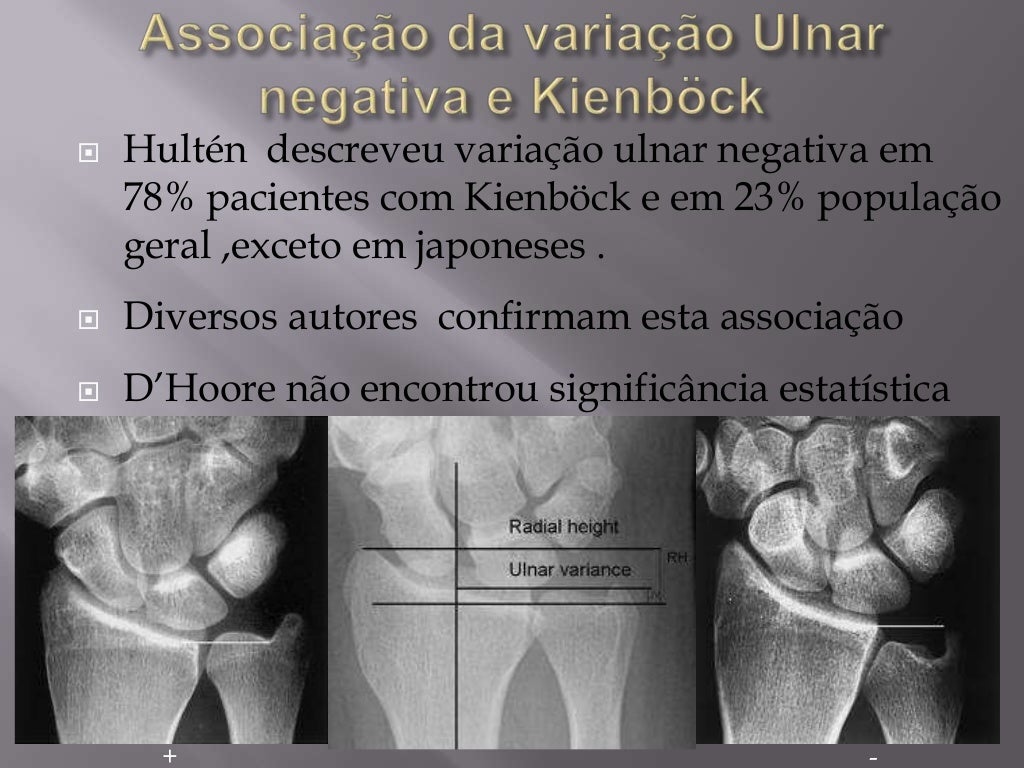

Introdução: A osteomalácia do semilunar é o resultado de uma interrupção traumática do suprimento sanguíneo para o referido osso, com uma perturbação subsequente de sua nutrição, caracterizando a Doença de Kienböck (DK). A etiologia da doença ainda é controversa, e dentre as principais teorias sobre o mecanismo para o desenvolvimento da osteonecrose do semilunar inclui-se.

Abstract. Avascular necrosis of the lunate, commonly known as Kienböck's disease is a disorder that can lead to carpal collapse and the need for surgeries, which can stabilize the wrist. There are different associations with the disease but the exact etiology is unknown. Kienböck's disease is believed to result from mechanical and.

Abstract. Kienböck's disease is a rare disease described as progressive avascular osteonecrosis of the lunate. The typical manifestations include a unilateral reduction in wrist motion with accompanying pain and swelling. Besides recent advances in treatment options, the etiology and pathophysiology of the disease remain poorly understood.

A doença de Kienbock é mais comum em pessoas com variância ulnar positiva. Ela pode ter que ser corrigida em uma eventual indicação para cirurgia. A tomografia e a ressonância magnética, por outro lado, têm a vantagem de ser mais sensíveis. Eles mostra os sinais da Doença de Kienbock em uma fase mais precoce do que as radiografias.

A doença de Kienböck é de nida por necrose avascular do semilunar e afeta, preferencialmente, indivíduos entre os 20 e 40 anos do sexo masculino. A siopatologia é multifatorial.